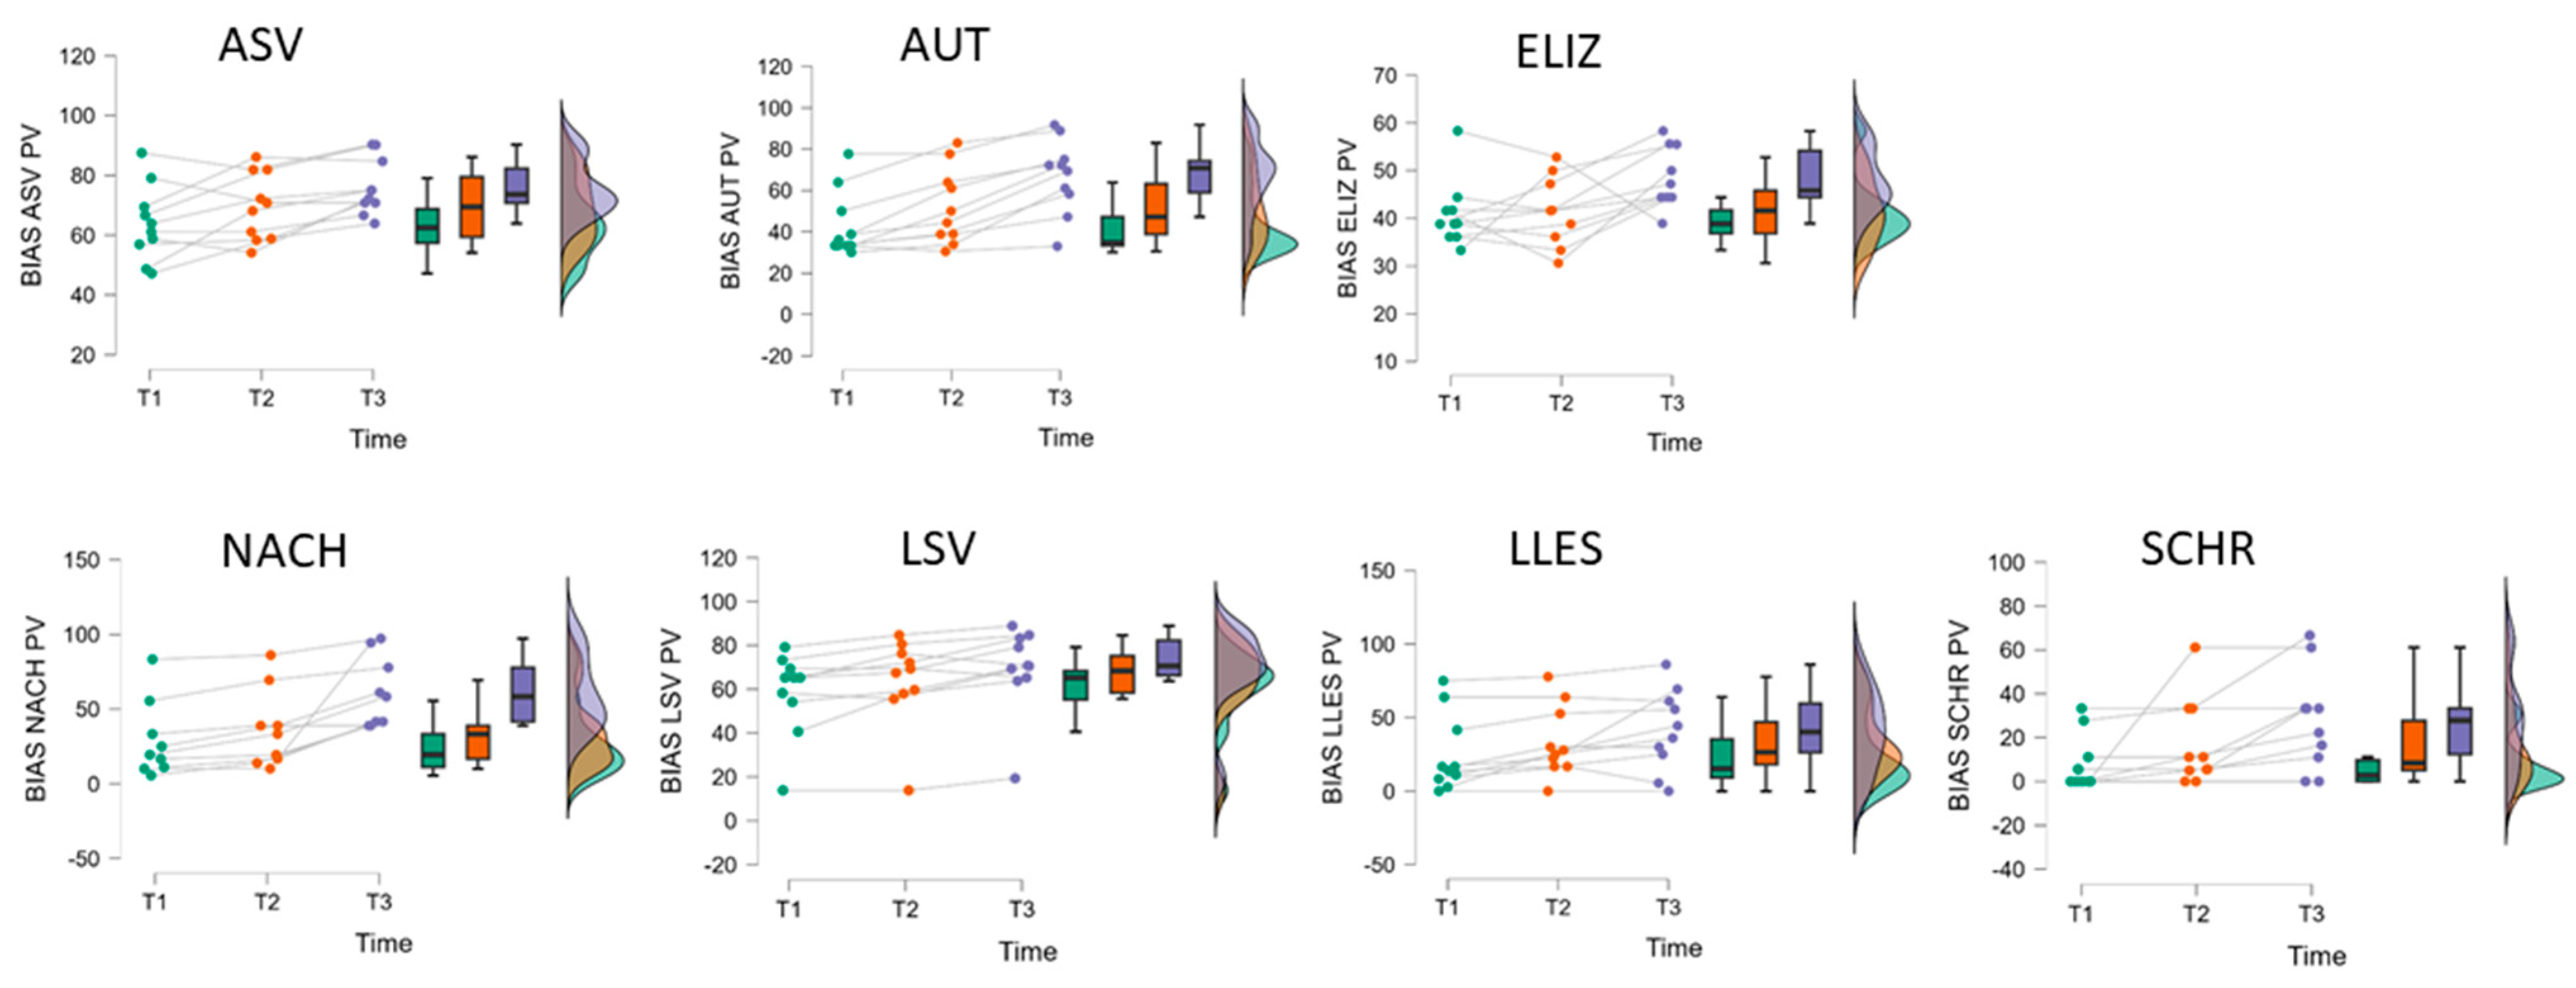

| B | Assessment | Difference | |||||||

| BIAS | T1 | T2 | T3 | Period 1 | Period 2 | Period 2 − 1 | Period 1 + 2 | ||

| (n = 10) | M (SD) | M (SD) | M (SD) | M (SD) | M (SD) | M (SD) | M (SD) | ||

| Profile level | 37.40 (3.81) | 39.35 (2.97) | 42.35 (2.45) | 1.95 (1.52) | 3.00 (1.39) | 1.05 (1.50) | 4.95 (2.50) | ||

| ASV | 63.91 (12.57) | 69.33 (11.26) | 75.95 (9.35) | 5.42 (3.60) | 6.62 (5.70) | 1.20 (12.40) | 12.04 (10.82) | ||

| AUT | 42.98 (15.98) | 52.22 (18.39) | 66.90 (17.86) | 9.25 (8.96) | 14.68 (8.51) | 5.44 (12.53) | 23.93 (12.18) | ||

| ELIZ | 40.80 (6.94) | 41.37 (7.11) | 48.31 (6.31) | 0.57 (7.72) | 6.94 (8.80) | 6.37 (11.76) | 7.51 (11.65) | ||

| NACH (n = 9) | 28.88 (25.39) | 36.30 (26.12) | 61.09 (23.57) | 7.42 (5.38) | 24.79 (24.05) | 17.36 (26.79) | 32.21 (22.28) | ||

| LSV | 58.49 (18.94) | 63.79 (20.00) | 69.54 (19.59) | 5.30 (5.90) | 5.75 (6.62) | 0.45 (10.00) | 11.05 (7.55) | ||

| LLES | 24.97 (26.14) | 33.28 (24.01) | 41.32 (27.51) | 8.31 (7.83) | 8.04 (15.85) | −0.27 (16.68) | 16.35 (18.61) | ||

| SCHR | 8.33 (12.35) | 16.60 (19.80) | 27.73 (22.83) | 8.27 (18.94) | 11.13 (12.53 | 2.86 (26.20) | 19.40 (18.58) | ||